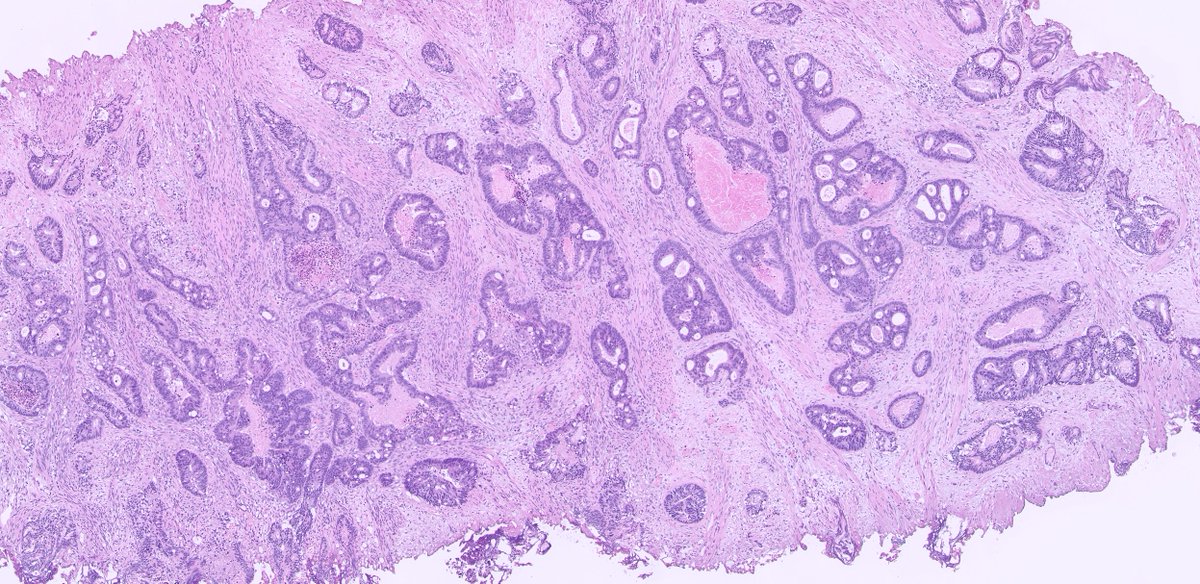

56/ M lung mass. Core biopsy from the lesion. CT and Xray findings attached . Kindly provide your valuable opinions. #pathtwitter #pulmonarypath